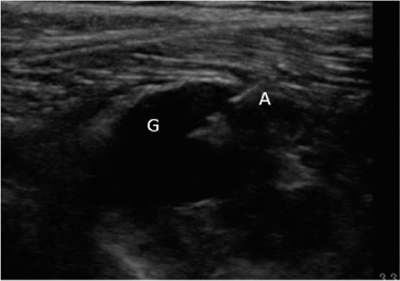

Se diagnosticó, por lo tanto, paresia de nervio peroneo derecho secundario a compresión por ganglión de articulación tibio-peronea proximal y se propuso al paciente un manejo intervencionista del mismo, que aceptó. Se realizó drenaje ecoguiado empleando una sonda lineal de alta frecuencia (10-5 MHz), una aguja de 20 G y una jeringa roscada de 5 ml (Figura 2), retirándose sin dificultad 1,5-2 ml de contenido mucinoso compatible con ganglión. Posteriormente se realizó infiltración de 1 ml de triamcinolona 40 mg ml diluida en 0,5 ml de mepivacaína al 2 %. Tras el procedimiento se evidencia una clara disminución del tamaño del ganglión.

Fig. 2. Ecografía en corte longitudinal de aspiración con aguja ecoguiada del ganglión. G: ganglión. A: aguja en interior de ganglión iniciando aspirado.